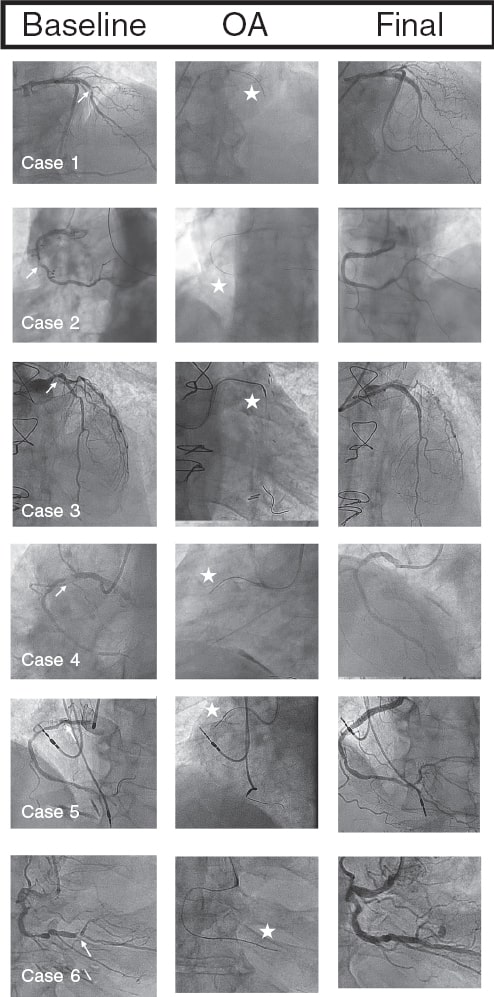

In all our cases, OA was successful, with the crown crossing the lesion and allowing subsequent angioplasty without major complications. Figure 1 illustrates the angiographic images of each case.

Figure 1. Baseline coronary angiography, orbital atherectomy (OA), and final coronary angiography. The arrows point to the uncrossable lesion, and the stars indicate the OA crown.